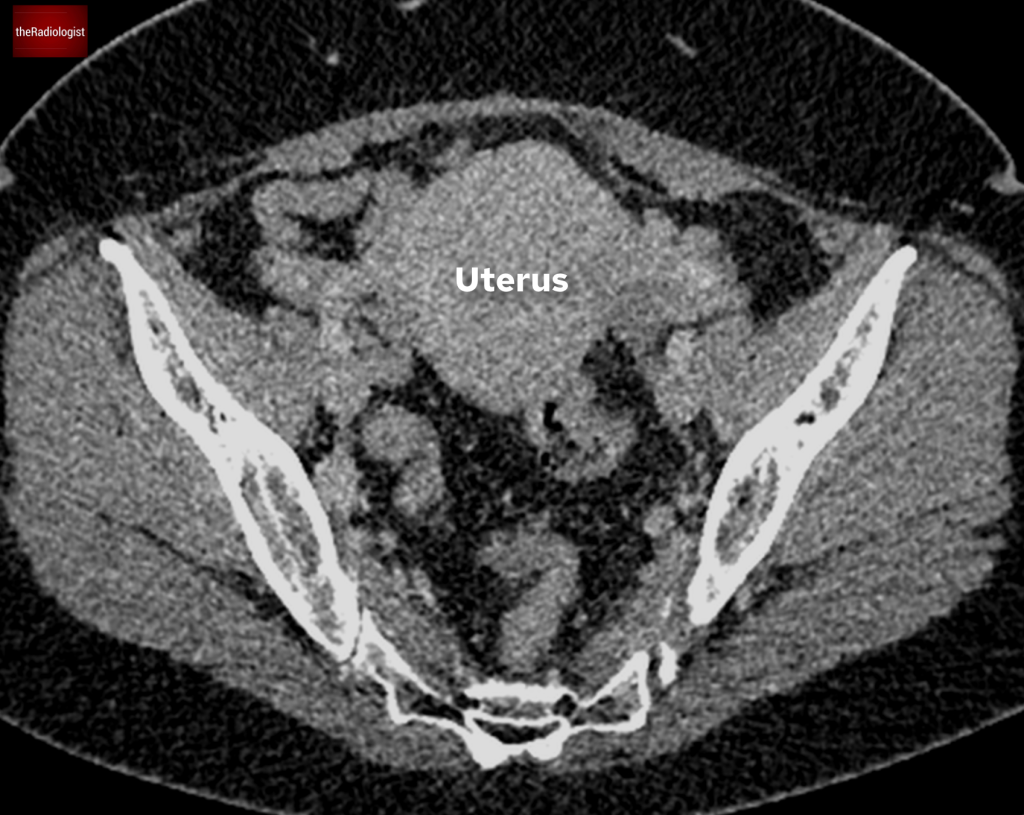

The only additional significant finding was of an enlarged uterus suggesting the presence of uterine fibroids.

Body CT also showed an enlarged uterus.